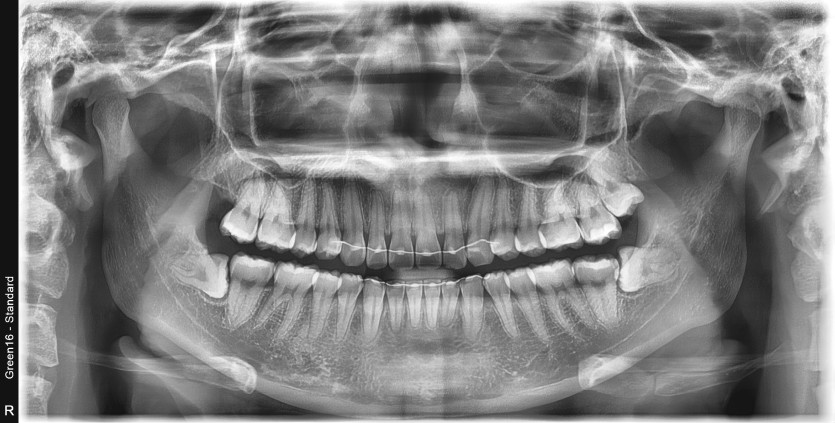

#28,38 사랑니 발치

구강 외과 전문의가 당일 발치했습니다.